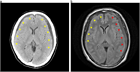

1. フレイルによる慢性硬膜下血腫の再発率や機能予後への影響(Pahwa B, et al. World Neurosurg X. 2024 Mar 29;23:100372. PMID: 38638610.,Gajjar AA, et al. J Clin Med. 2025 May 4;14(9):3176. PMID: 40364207.)

1. 再発慢性硬膜下血腫に対する中硬膜動脈塞栓術

1. 慢性硬膜下血腫における早期加入の有用性(Knuutinen O, et al. World Neurosurg. 2025 May;197:123843. PMID: 40024327.)